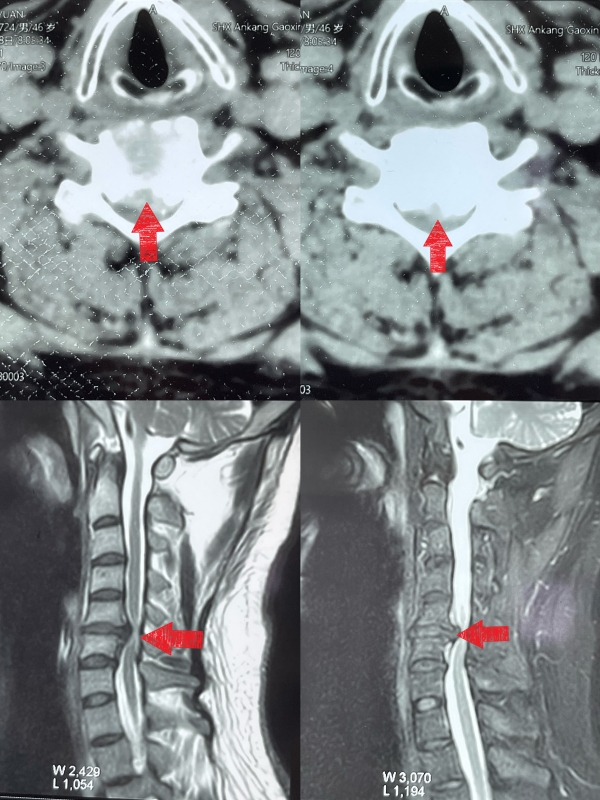

该患者为46岁的男性,长期受到颈椎疼痛的困扰。此次疼痛加剧后,明显出现双下肢无力行走不稳,双上肢麻木及疼痛,于是他慕名来到西安交通大学第二附属医院骨三科就诊。经过详细的检查和影像学检查后,王伟卓医生发现患者颈椎间盘突出压迫了脊髓神经组织,导致颈部疼痛难忍、活动受限等症状。

为了迅速缓解患者的症状,经过评估,王伟卓主任医师建议患者纳入颈椎间盘突出ERAS手术流程。这种手术是通过切除压迫神经组织的突出椎间盘来恢复其颈部的正常功能。12日在手术过程中,张纯主任主刀、王伟卓主任医师、黄思华医生配合,使用了精细的技术及精湛的技艺,逐层切除了突出的颈椎间盘,并植入了零切迹人工椎间盘,完成了颈椎椎间融合,同时保留了周围组织和器官的功能。经过2个小时的细致操作,终于完成了这次复杂的手术,最终术中出血量仅50ml,全程未输血。